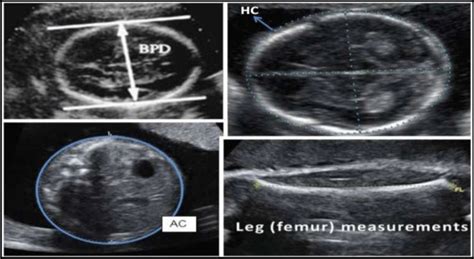

Alright, let’s get down to brass tacks. During your 29-week ultrasound, your healthcare provider will measure several aspects of your baby’s size and development. These measurements, often presented as acronyms, give doctors a snapshot of how your little one is growing. The primary measurements include BPD (Biparietal Diameter), HC (Head Circumference), AC (Abdominal Circumference), and FL (Femur Length) . These measurements are crucial as they help estimate the baby’s gestational age, weight, and overall well-being. Knowing the normal ranges for each measurement at 29 weeks is essential, and we’ll explore those in detail.

BPD stands for Biparietal Diameter , which is the measurement of your baby’s head across from one parietal bone (side of the skull) to the other. It’s like measuring the width of the head. It’s one of the earliest measurements taken during pregnancy, and it’s a reliable indicator of fetal age during the first and second trimesters. At 29 weeks, a normal BPD typically falls within a specific range, indicating that the baby’s head size aligns with the expected gestational age. Variations can occur, and it’s essential to understand that these are estimations. Your doctor considers all measurements in context, not just BPD alone.

HC , or Head Circumference , measures the distance around your baby’s head. It’s like measuring the circumference of the head using a virtual tape measure. This measurement is another vital indicator of fetal development, reflecting how the baby’s brain and skull are growing. Much like BPD, HC is compared against established gestational age norms to assess whether the baby’s head size is appropriate for the stage of pregnancy.

AC , which means Abdominal Circumference , measures the circumference of your baby’s abdomen at the level of the stomach. This measurement provides insights into the baby’s abdominal development and can provide an estimate of the baby’s weight. The AC measurement can be particularly sensitive to factors like the baby’s nutritional intake and any potential growth restrictions.

FL stands for Femur Length , and it measures the length of your baby’s femur, which is the thigh bone. This measurement is a good indicator of the baby’s overall skeletal development and provides another piece of the puzzle to estimate the baby’s gestational age. The femur is a long bone, and its length offers a straightforward way to evaluate how well your baby’s bones are developing.